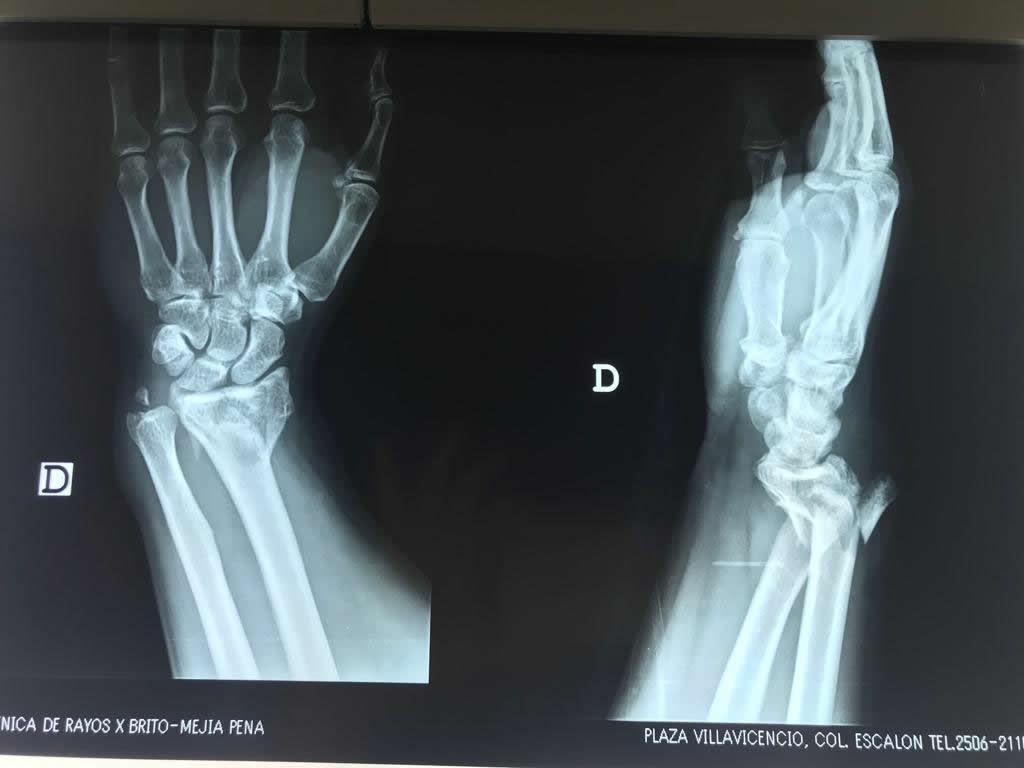

Los procedimientos más comunes en cirugía de la mano son aquellos destinados a reparar traumatismos, incluyendo lesiones de tendones, nervios, vasos sanguíneos, y articulaciones; huesos fracturados; y quemaduras, cortes, y otros daños de la piel.